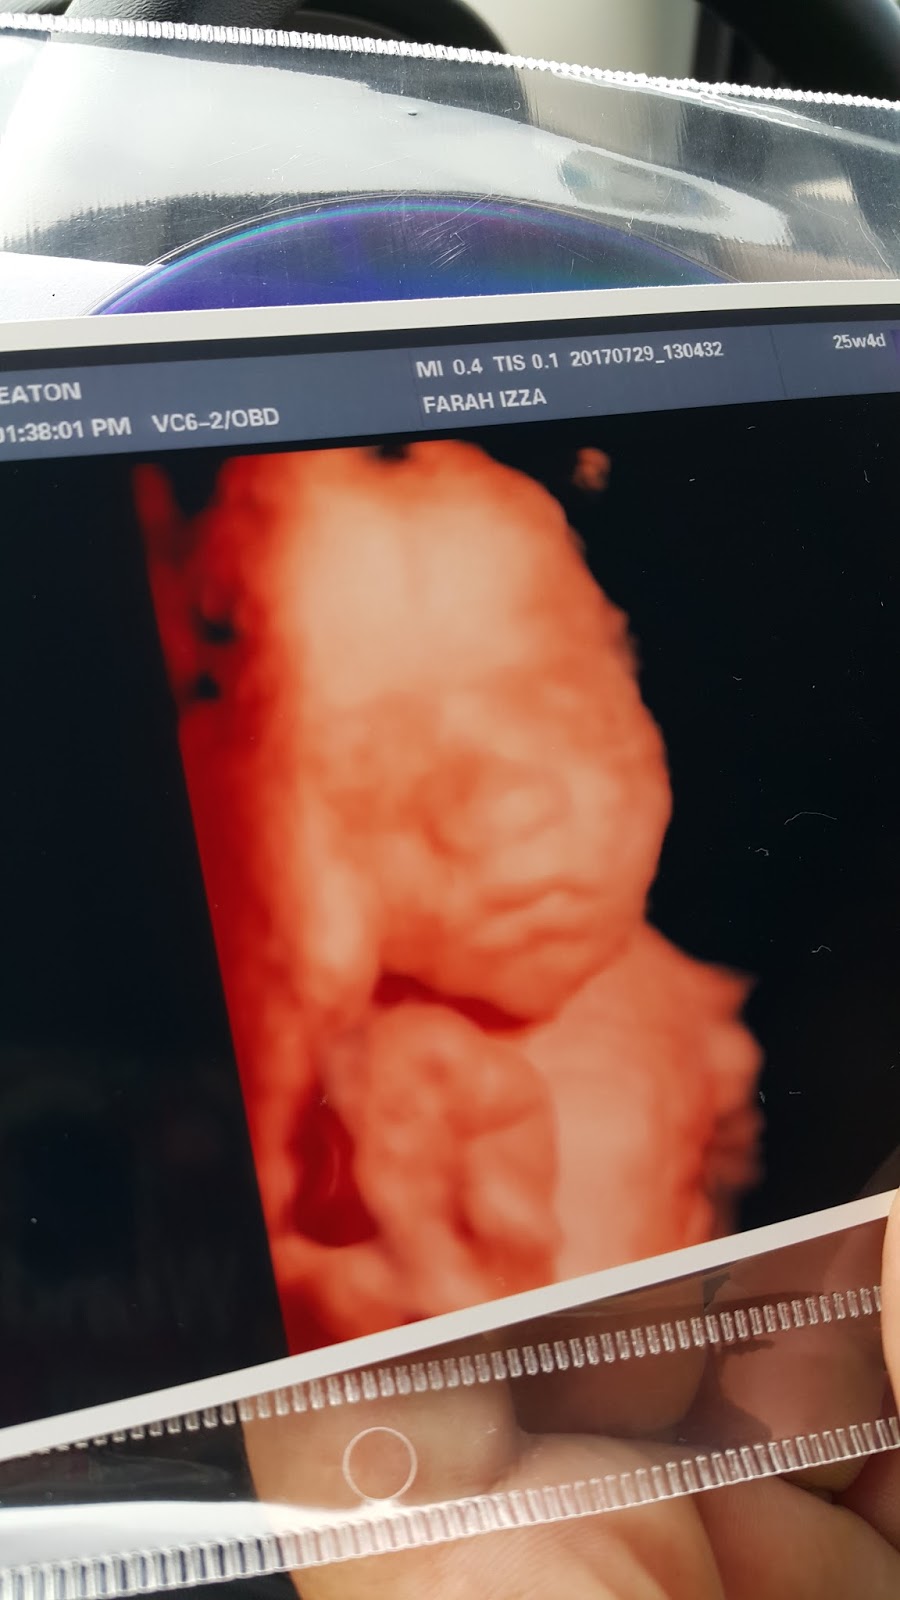

We were greeted by a very nice young sonographer who'd took the time to explain to us Baby R's progress and patiently answered all of the children questions about the baby. She took time to ensure that we have a cute photo of Baby R and we are extremely happy with the outcome of the scan. Alhamdullilah everything looks good and we spend a good 30 mins in there.

For the price of RM230, we have Baby R's scans in color (1 printed and others in a CD). Also a report for the detail scan. Overall, if you don't mind the wait, I'd say try out the scan in Klinic Jameaton to meet your little bundle of joy. :)